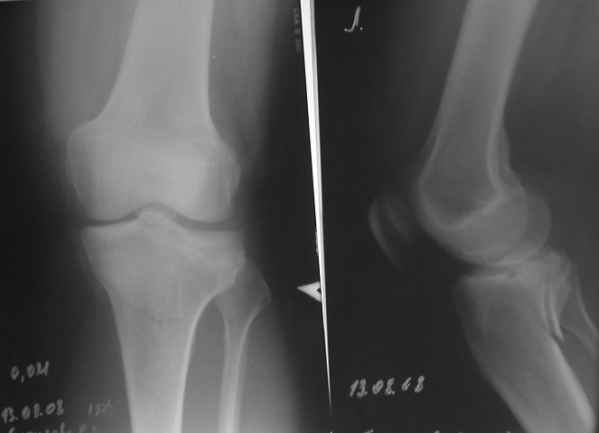

конечно есть, просто не дошли. Посылаю

Действительно, доступ капризный. Из имплантов я бы выбрал Tomofix от синтез.

Проблема тут, видимо, не в выборе имплантата, а в том, что надо делать остеосинтез задним доступом. А пластинка подойдет практически любая - небольшая T-образная, хоть две 1/3 трубчатых. Угловая стабильность необязательна. Лишь бы трансплантат не вываливался. На КТ хорошо бы увидеть еще и срезы в сагиттальной и фронтальной плоскостях.

Если целая я советовал бы ограничиться минимальным объемом вмешательства - компрессионные винты спереди. Только надо

тщательно подобрать размер и винтов и их резьбовой части.

При повреждении задней крестообразной связки - ревизия из заднего доступа, обычно фрагмент с основанием достаточно большой и его можно

зафиксировать двумя винтами. Если же надо восстанавливать связку - можно из этого-же небольшого заднего доступа и отломок "привязать" протезом.

Этой фиксации достаточно, срастется. "Tomofix" мне представляется здесь избыточной, а сзади еще

ставить муторно.